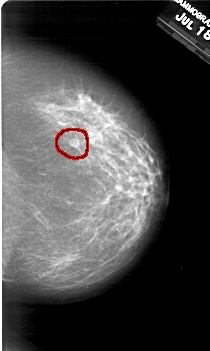

A_2001_1.RIGHT_MLO

RIGHT_MLO LINES 6151 PIXELS_PER_LINE 3976 BITS_PER_PIXEL 12 RESOLUTION 43.5 OVERLAY

FILE: A_2001_1.RIGHT_MLO.OVERLAY

TOTAL_ABNORMALITIES 1

ABNORMALITY 1

LESION_TYPE MASS SHAPE OVAL MARGINS OBSCURED

ASSESSMENT 2

SUBTLETY 3

PATHOLOGY BENIGN

TOTAL_OUTLINES 1

BOUNDARY